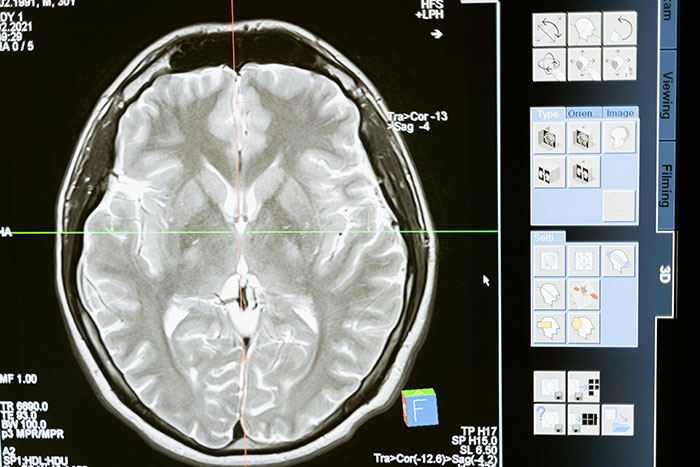

#16

At any moment anyone can just randomly drop dead from a brain aneurysm. It’s more or less common for certain people, but it can literally happen to anyone at any age at any time.

Image credits: ShadoOwEd